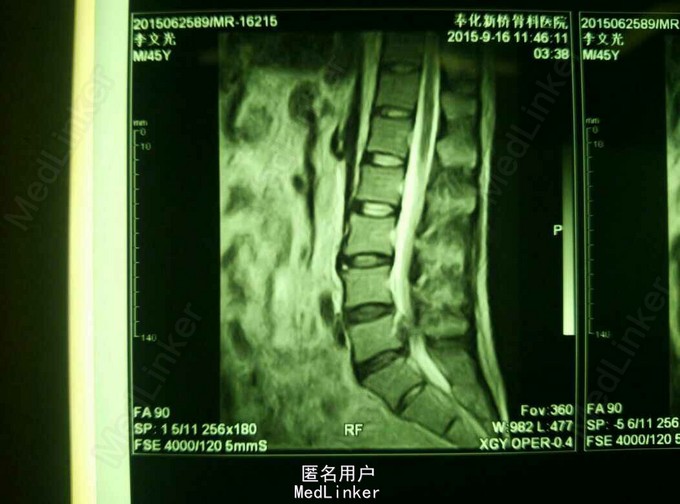

查体:脊柱无畸形,腰部L5S1间隙处轻压痛,脊柱无叩击痛,右小腿外侧及足底触痛觉减退,右下肢肌力4级,右下肢直腿抬高试验40度。 MRI提示:L5S1椎间盘脱出,髓核游离要椎管。

诊断:L5/S1椎间盘脱出(右侧) 治疗:因保守治疗效果不佳,准备行手术治疗。

请大家谈谈该患者的手术方案:开放融合内固定术?椎间盘镜手术?椎间孔镜手术?还是其他方案?